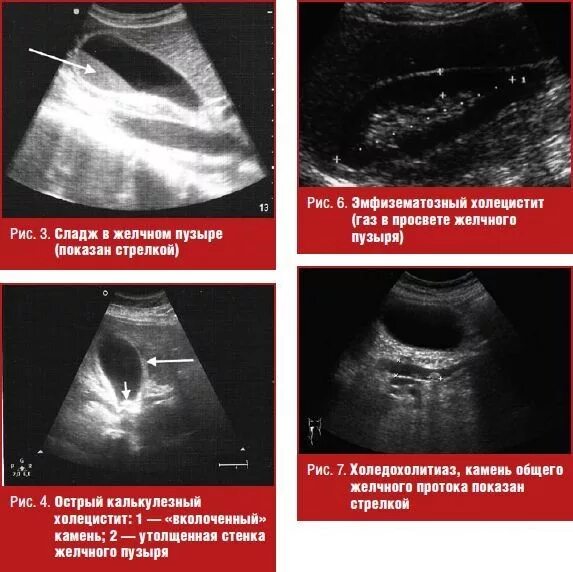

Диффузные изменения стенок желчного пузыря